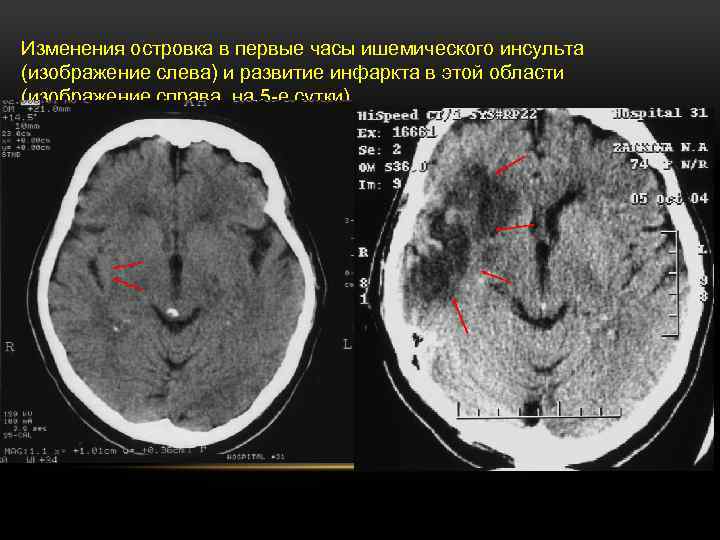

Изменения островка в первые часы ишемического инсульта (изображение слева) и развитие инфаркта в этой области (изображение справа, на 5 -е сутки).